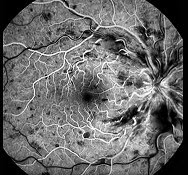

D.为不可逆的视神经损害

该图是何种疾病的荧光造影图()

A.视网膜中央动脉阻塞

B.视网膜中央静脉阻塞

C.视网膜分支动脉阻塞

D.视网膜分支静脉阻塞

E.视网膜静脉周围炎